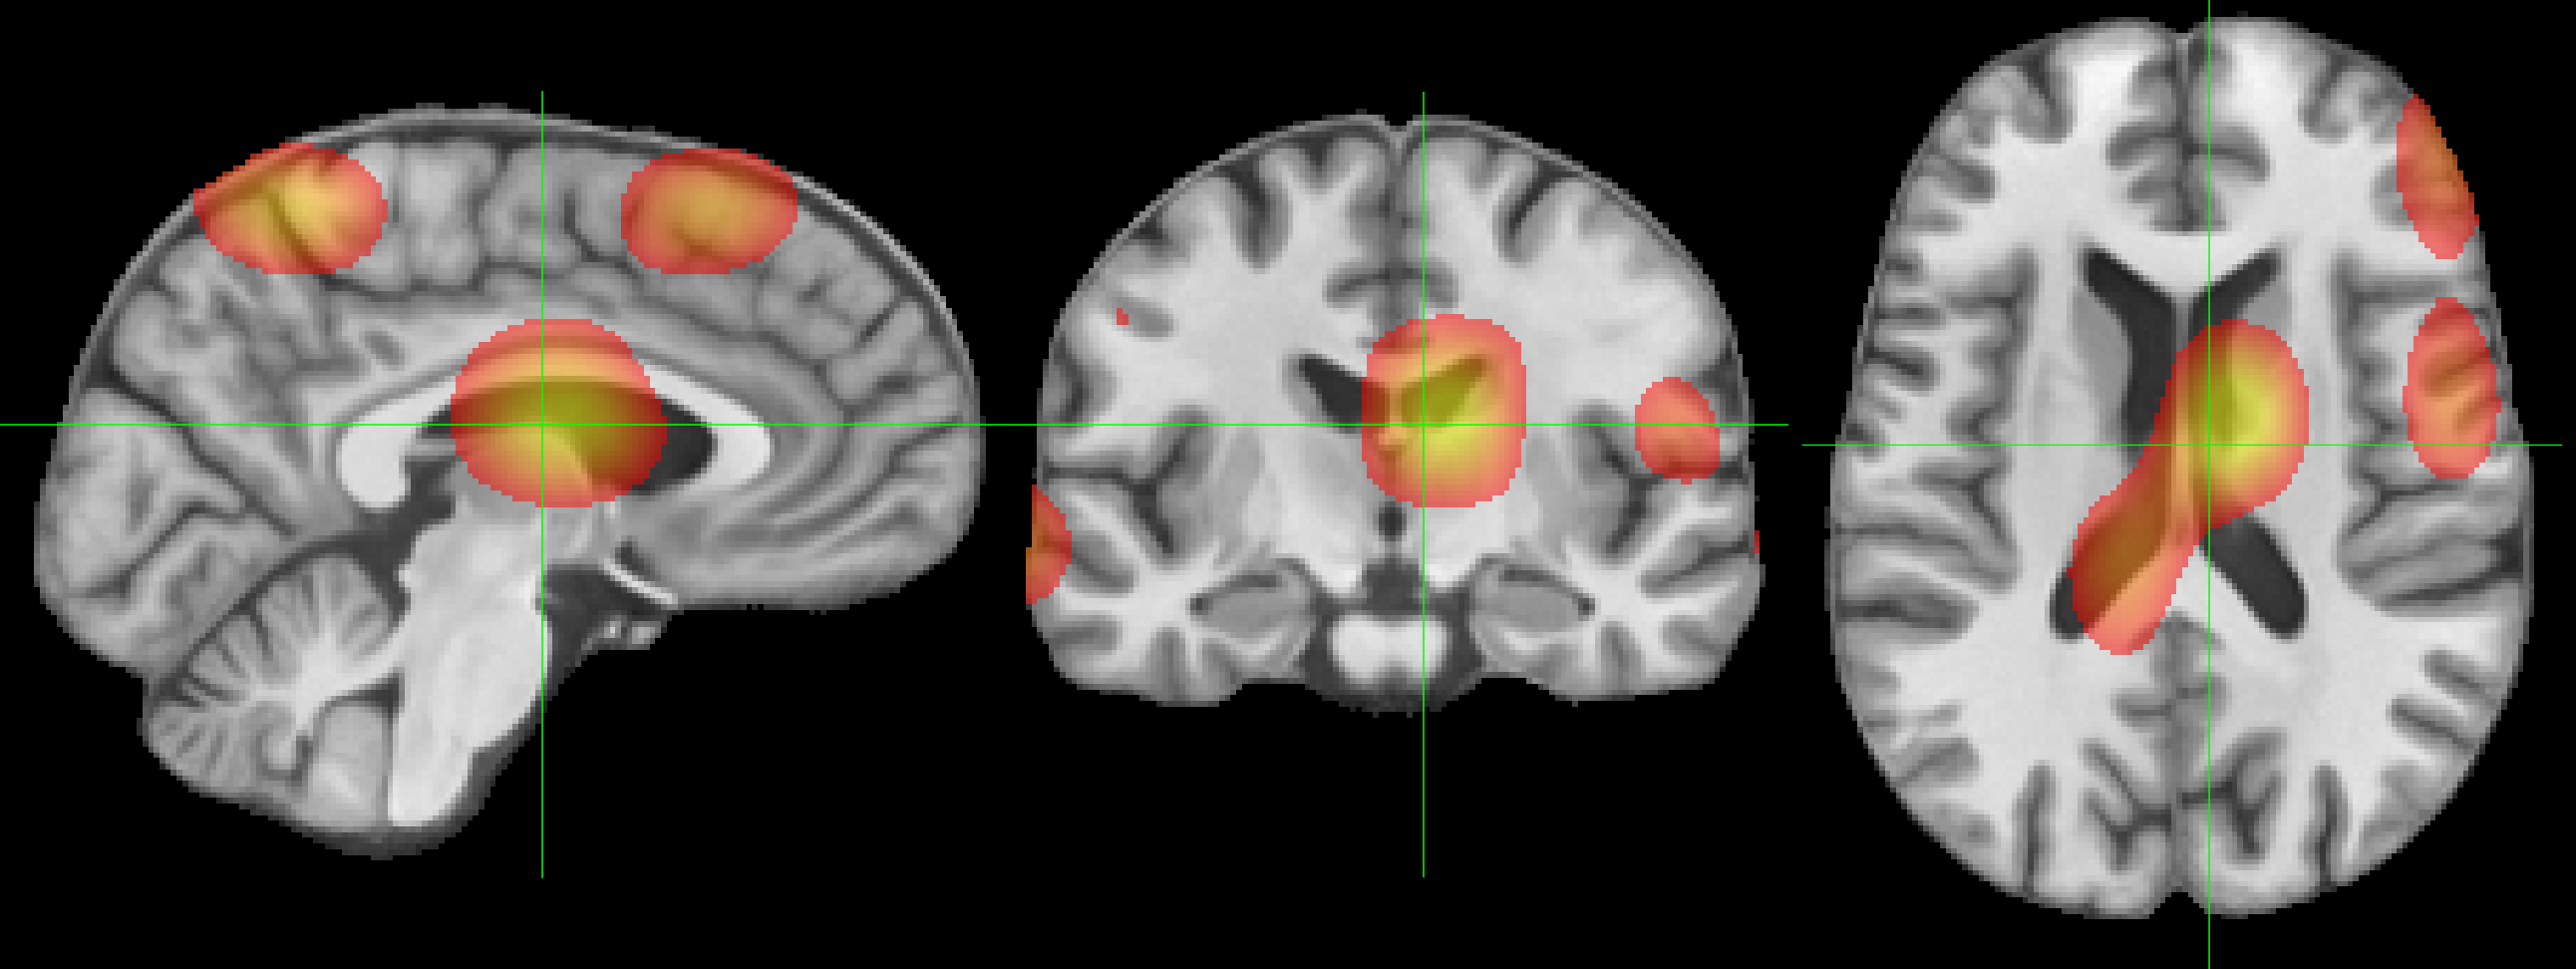

(b) MINiT Attention Map

Refer to caption \phantomcaption

Figure 6: Attention maps learned by (a) NiT and (b) MINiT models. The bar shows the color-map (from red =0.4absent0.4=0.4 to yellow =0.8absent0.8=0.8; thresholded on the lower bound for clarity).

We compute the attention maps for the base NiT from the output token to the input space using Attention Rollout [1]. For MINiT, we use Attention Rollout to calculate attention weights for each patch in a block, which we concatenate and then average to build attention weights for a block. We proceed to use Attention Rollout using the block attention weights to compute the final attention maps. From Fig. 6, we observe that MINiT attends between numerous different voxels in the neuroimage (due to MIL nature), in contrast to the focused attention between fewer, but larger, voxels by the base NiT. Considering existing documented evidences [21] that sex differences in youth are widespread in the brain and the significant difference in accuracy between the two models, it is evident that MINiT is able to better generalize by capturing features spread all around the brain.